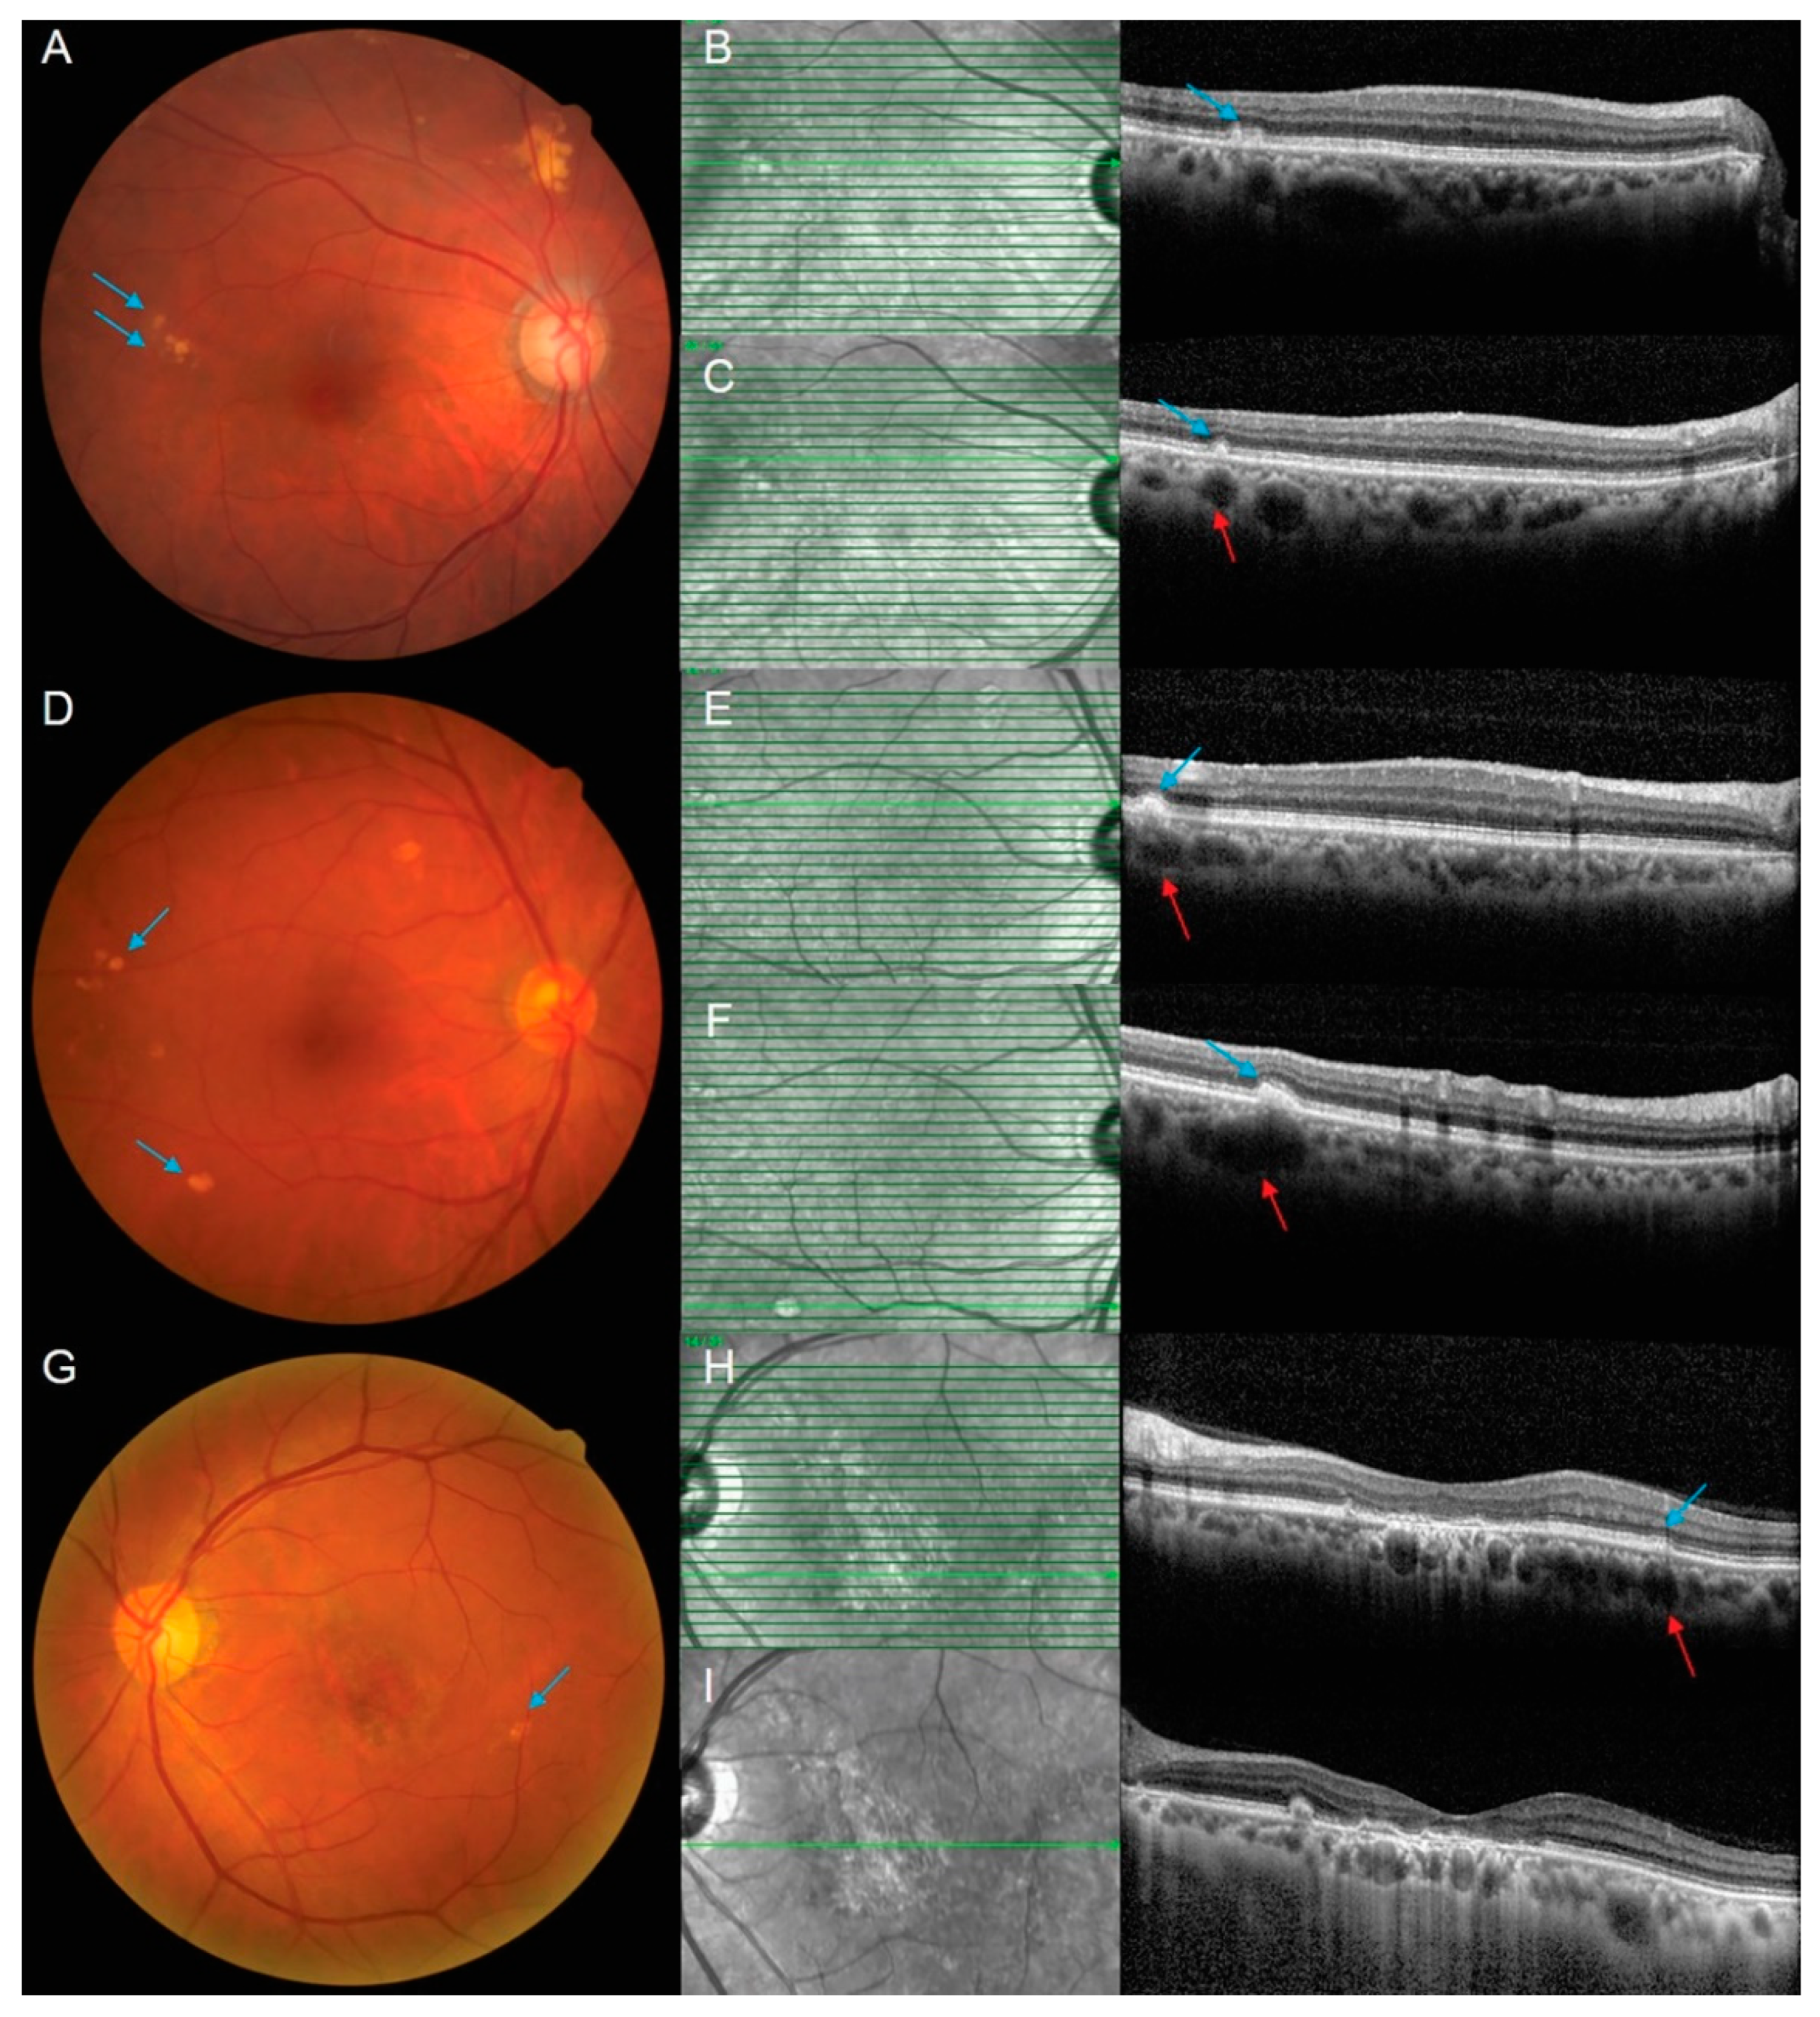

| Pachydrusen associated with pachyvessel | 29/47 (62%) | 38/57 (67%) |

| Pachydrusen without associated pachyvessel | 18/47 (38%) | 19/57 (33%) |

| Pachydrusen associated with pachyvessel | 13/21 (62%) | 16/26 (62%) |

| Pachydrusen without associated pachyvessel | 8/21 (38%) | 10/26 (38%) |